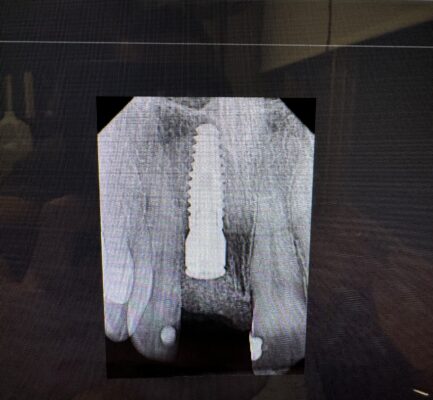

Guide failed, freehand placement immediate #8. First 2 sizes I wanted were sinkers. Finally got a larger one super deep as a spinner so grafted and left it. How can I salvage this when it comes time uncover/restore or am I gonna have to take it out? buccal lingual position is in screw retained position. Thank you

If there is enough bone and biology around it and the body heals well should be straightforward. You’ll just have to remove bone that heals over the top which is a good problem to have and it’s pretty straightforward.

Hey man, thanks for sharing here! First off, no I don’t think you’re going to have to take this implant out. I think it’s gonna turn out just fine.

Secondly, you might not have as much bone as you think covering the implant. If that’s graft on top of the screw, it might resorb a few mm.

Be prepared to remove and shape bone a little bit for the surgery. I would recommend the round-gold diamond drill from implant club. You might end up spending a good 20 min just shaping that bone so that you can securely and passively get a scan body/impression coping on.

The worst case scenario in this case might be that the platform is a bit apical and the gum recedes a little.